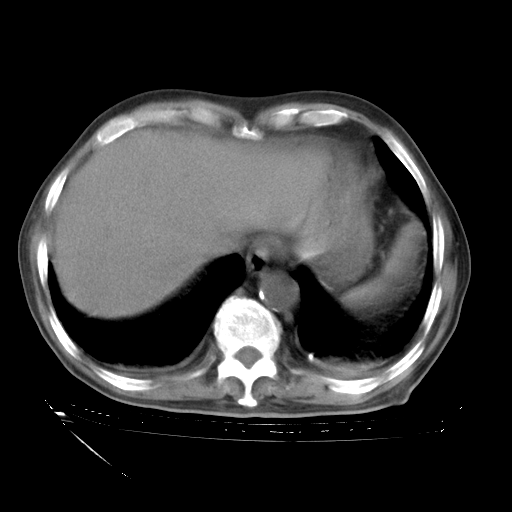

补充下:5月9日胸部CT:似乎已见双下肺胸腔积液了,鉴于目前有下肢水肿,肝功示:白蛋白低,应注意多浆膜腔积液(漏出液可能大?),需注意!

甲强龙80mg/日+抗结核治疗(异烟肼+利福霉素+乙胺丁醇)10天。复查肺部CT。

治疗10天肺部CT